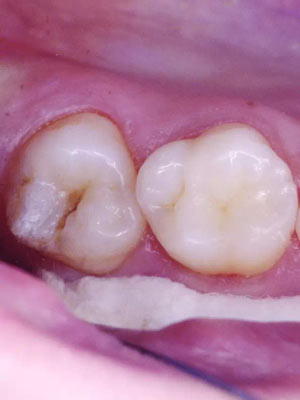

窩溝封閉前后

窩溝封閉前

易患齲的深窩溝和早起齲損